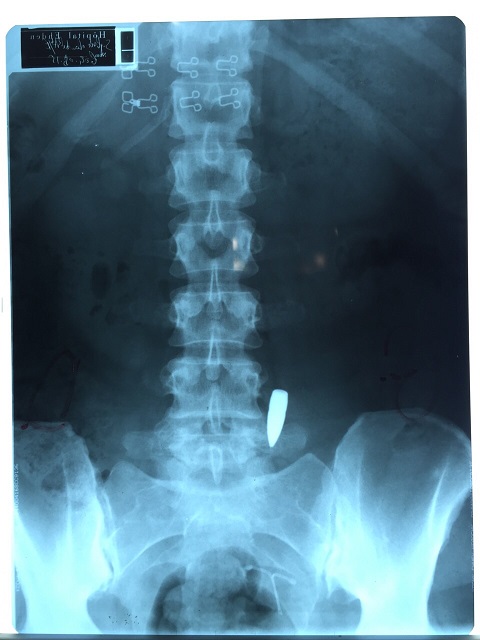

دهمت قوة من الجيش اللبناني فجر اليوم عددا من المنازل في إهدن وأوقفت بعض المشتبه بهم بإطلاق النار في حفل “وداع العزوبية” للضابط ريمون عزيزي وآلي ـ جو أبي زيد، ما أدّى الى إصابة طبيبة بلجيكية متأهلة من الطبيب لوسيان فنيانوس برصاصة طائشة في ظهرها أثناء تناولها العشاء في أحد المطاعم في شارع المغتربين في إهدن.